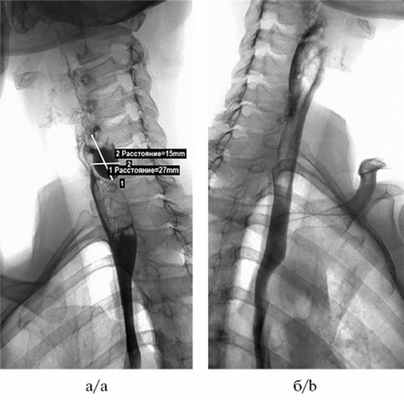

Перед хирургическим вмешательством выполняли рентгеноскопию пищевода, желудка и эндоскопическое исследование для оценки размеров дивертикула, состояния слизистой оболочки дивертикула. Размеры дивертикулов по данным рентгеноскопии варьировали от 15 до 50 мм (медиана 30 мм). Распределение пациентов по размеру дивертикула при эндоскопическом исследовании представлено в табл. 2.

Рис. 3. Рентгеноскопия пищевода до операции: определяется дивертикул с задержкой контрастного вещества в нем (а); проходимость восстановлена, «задержка» контрастного вещества не определяется (б).